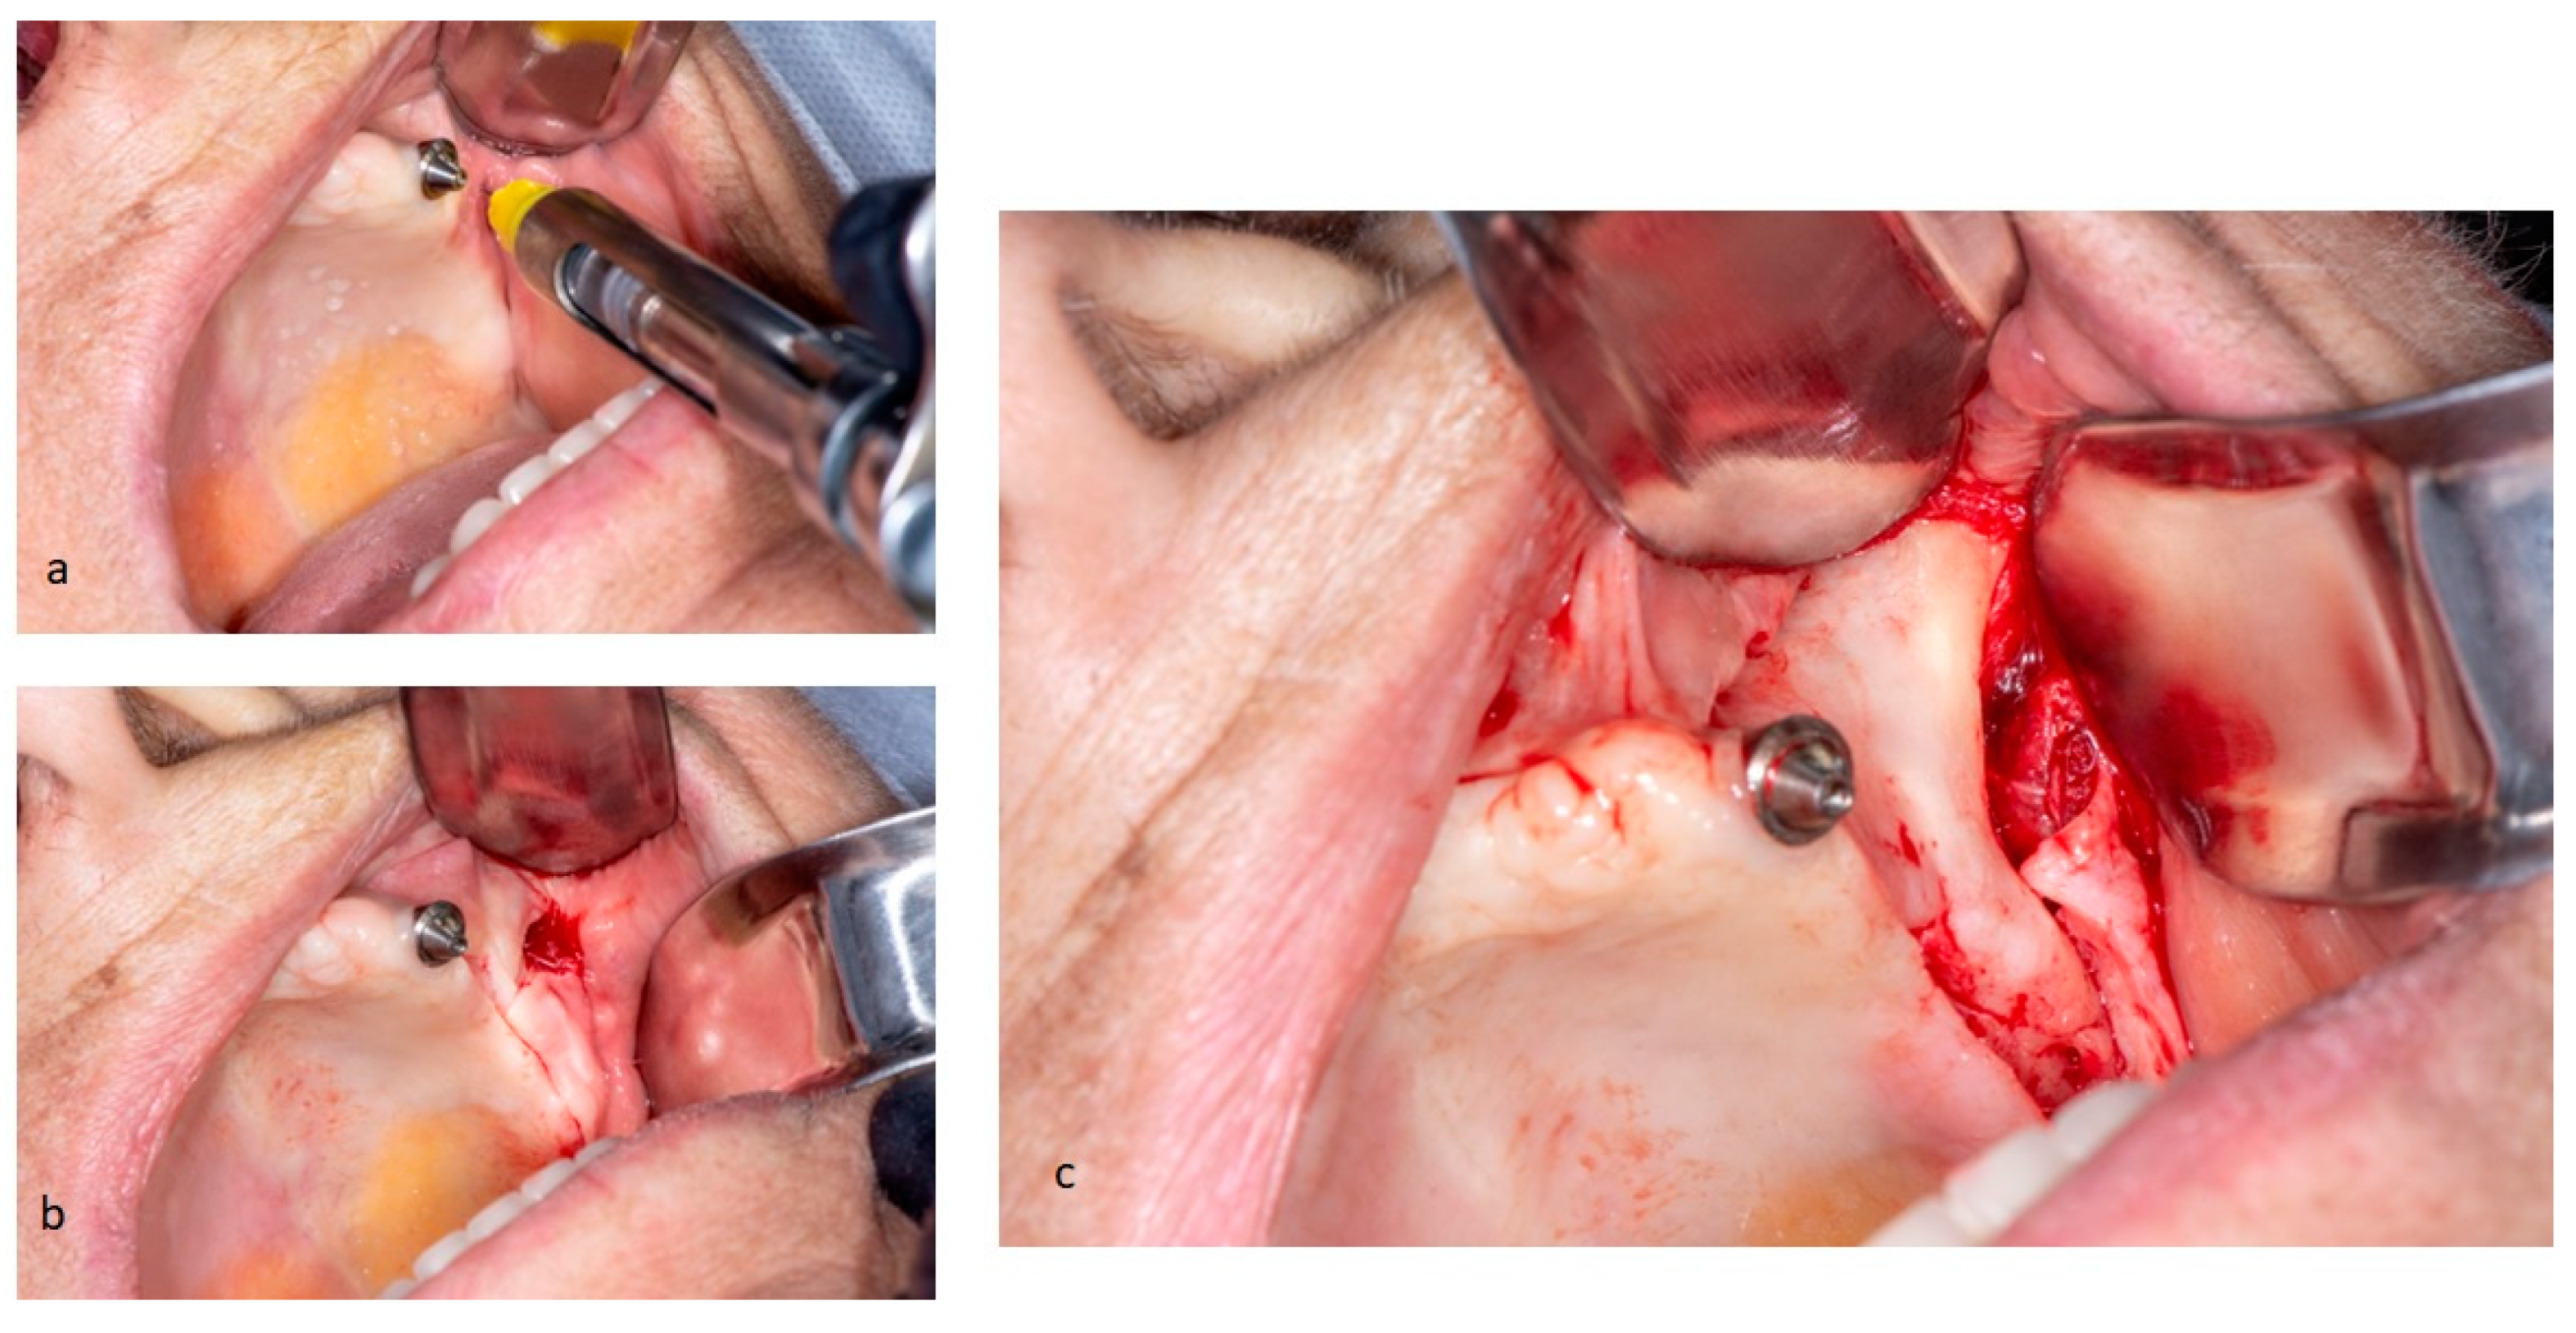

Upon patient acceptance, she was admitted in an outpatient setting to undergo the surgical procedure, performed with local anesthesia. A small incision was made in the alveolar crest, from the right region of the first molar to the left, preserving the descending palatine artery, which, due to anatomical evolution of the atrophic maxilla, changes its position. Two posterior vestibular incisions were performed bilaterally, considering the appearance of Parotid duct, in order not to cause accidental injuries, and finally, a median release incision was made below the nasal column. Subsequently, a mucoperiosteal flap was simultaneously raised bilaterally along the entire incision. Reflection of mucoperiosteal flap may be performed in two different manners, depending on the surgical procedure involved: placement of only two implants in zygomatic bone or an all-on-four surgery. In surgical case of placement of two zygomatic implants, the mucoperiosteal flap is elevated to expose the alveolar crest, the anterolateral wall of maxillary sinus and the origin of zygomatic arch, where masseter muscle is inserted. However, in this case, mucoperiosteal flap from the paranasal region was elevated medially until the infraorbital nerve appeared. Infraorbital foramen is the posterior limit of mucoperiosteal reflection and visible bone, being exceeded only in special cases of need to reach the zygomatic notch and fully expose the external surface of the malar region, an area dedicated to implant site preparation.